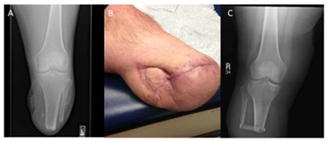

Transtibial amputation is the most commonly performed major limb amputation. Many of the patients have a realistic chance to ambulate post-operatively; the literature quoted varies from 17%-77% [11-14]. The transtibial amputation is not for every patient, those critically ill, debilitated, spastic, or currently with a knee flexion contracture will end up with a poor outcome because of an inability to transfer or sit. A more proximal knee disarticulation results in better outcomes in the spastic patient population. Various incisions have been described for the transtibial amputation, however, the long posterior myocutaneous flap has been proven to have good outcomes with few wound complications and a high likelihood of post-operative ambulation [15]. The ideal length for a transtibial amputation is to make the tibia osteotomy approximately 12 cm to 18 cm from the tibia tubercle [16]. Depending on whether the Ertl technique will be employed, which supporters argue improves weight distribution in the residual limb, the fibula osteotomy is performed either 4 cm distal to the tibia osteotomy to allow for fibular bone bridge creation, or 1 cm to 2 cm proximal to it. In a recent retrospective review, Brown et al., indicate that those patients undergoing the Ert l procedure had a higher rate of post-operative wound complications compared to those without the bone bridging part of the procedure [15]. A key component of the transtibial amputation is the myodesis, similar to the transfemoral amputation, however this involves tacking the soleus to the anterior tibial cortex through cortical drill holes. When the long posterior myocuteanous flap is delivered anterior, the muscle bulk of the posterior compartment pads the distal end of the residual limb while simultaneously moving the wound from the prosthesis-residual limb weight bearing interface. An appropriately designed flap has minimal “dog ears” and is nicely tapered to optimize the fit for the prosthesis (Figure 2).

Figure 1: AP radiograph of the right femur following transfemoral amputation with drill holes in the distal femoral diaphysis for the adductor myodesis.

Figure 2: (A) AP radiograph of the knee following transtibial amputation. (B) Clinical picture of a healed transtibial amputation using a long posterior myocutaneous flap that required skin grafting for complete coverage. (C) AP radiograph of the knee following the Ertl technique performed during a transtibial amputation.